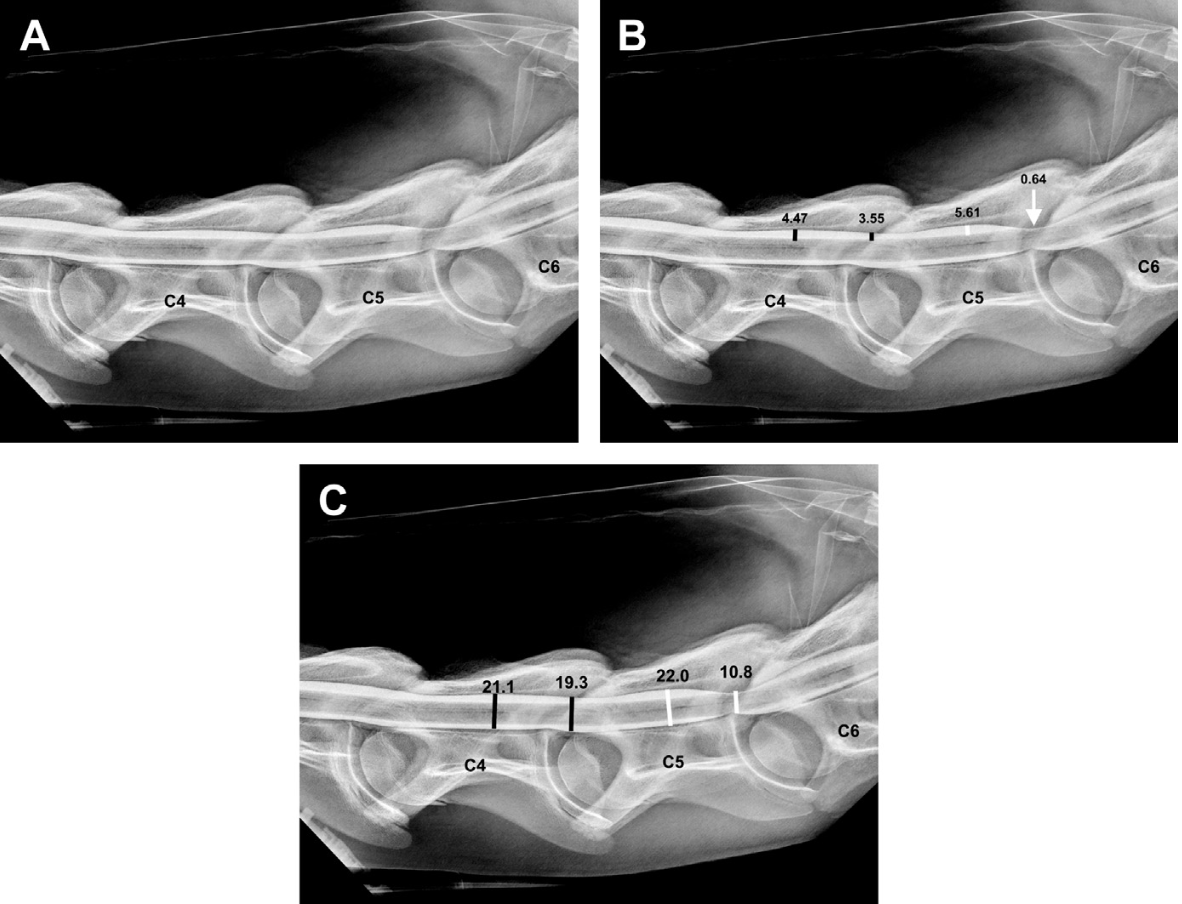

What are the intra- and inter-vertebral sagittal ratios to diagnose CVSM ?

Intravertebral sagittal ratios : 0.52 for C3-C6, 0.56 for C6-C7 (Se 84%, Spe 32%)

Intra- and inter-vertebral sagittal ratios : 0.485 for C3-C7 (Se 20%, Spe 100%)

What are the ratios to diagnose CVSM using radiographic myelography ?

50% decrease in the height of the dorsal contrast column compared with cranial height (Se 71%, Spe 65%)

70% in the flexed view (decrease Se, increase Spe)

20% decrease in the total dural diameter of the contrast column compared with cranial diameter, in neutral position.

25% in the flexed view (Se 100%, Spe 100%)